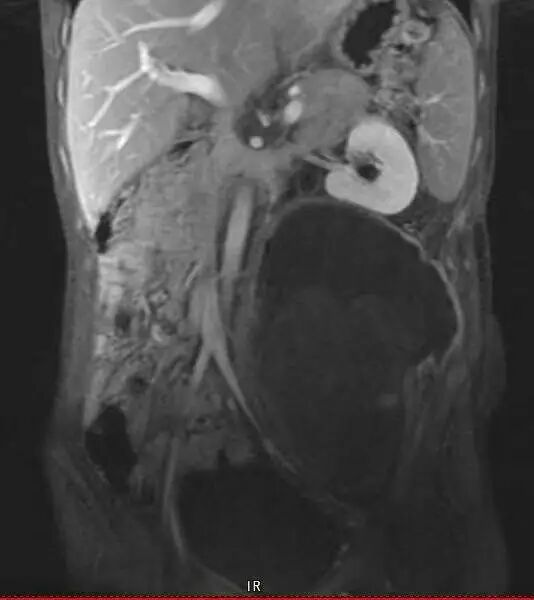

术前影像资料提示:患者左侧腹膜后存在一巨大恶性神经鞘瘤,最大径达20.1厘米。肿瘤已广泛侵犯周围结构,包括同侧髂骨、腰椎以及输尿管。